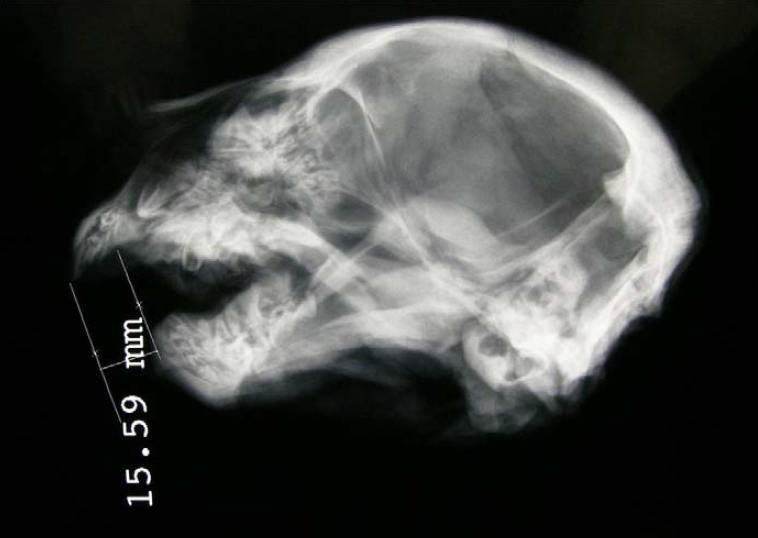

Certains chercheurs essayent de comprendre « pourquoi » les lions se mettent à manger des hommes. Toutes les pauvres bêtes des études que je viens de citer présentaient ainsi des problèmes dentaires (voir photo précédente)... Packer et al. (2005) propose plus simplement l’effet de l’augmentation de la densité humaine pour expliquer le nombre grandissant d’attaques depuis les années 1990, et nous présente une carte représentant la distribution de plus de 800 attaques depuis cette année là en Tanzanie… Eventuellement une idée des points chauds à éviter durant le prochain voyage touristique !

Commençons par la captivité. Saviez-vous qu’un lion élevé dans un zoo aura un cerveau plus petit qu’à l’état sauvage ? Une diminution comprise entre 3,5 et 10,5 % du volume crânien selon l’équipe de Yamaguchi (2006) qui s’est chargée de mesurer consciencieusement les crânes de 370 lions. Une différence qui serait bien due à la captivité en elle-même, et non aux conséquences de la consanguinité qu’elle implique souvent, puisqu’un lion né à l’état sauvage et élevé dans un zoo présentera également un cerveau plus petit. La consanguinité a pourtant bel et bien, elle aussi, des effets délétères. Prenez les lions blancs par exemple. Ces lions présentent un allèle mutant récessif qui leur confère une couleur allant du blond au blanc (il ne s’agit pas d’albinisme). Les adultes de ce type sont rares à l’état sauvage, d’autant plus qu’ils sont plus repérables par les proies et par les prédateurs lorsqu’ils sont lionceaux… Mais les humains sont avides de rareté (voyez ici), et on trouve des lions blancs à foison en captivité. Ce désir a un prix, et il est rude pour les lions. Dans un seul zoo par exemple ou des parents blancs ont donné naissance a 19 lionceaux, un seul a survécu jusqu’à l’âge adulte ! Parmi les autres, 4 sont mort-nés, 13 sont morts durant leur premier mois et le dernier a du être euthanasié à cause de son incapacité à saisir la nourriture. Une publication parue dans un journal vétérinaire (Scaglione et al. 2010) présente toutes leurs malformations à grand renfort de photos plutôt morbides… Entre troubles du comportement et multiples malformations au niveau du crâne, les effets de la consanguinité se font ressentir plus que jamais.